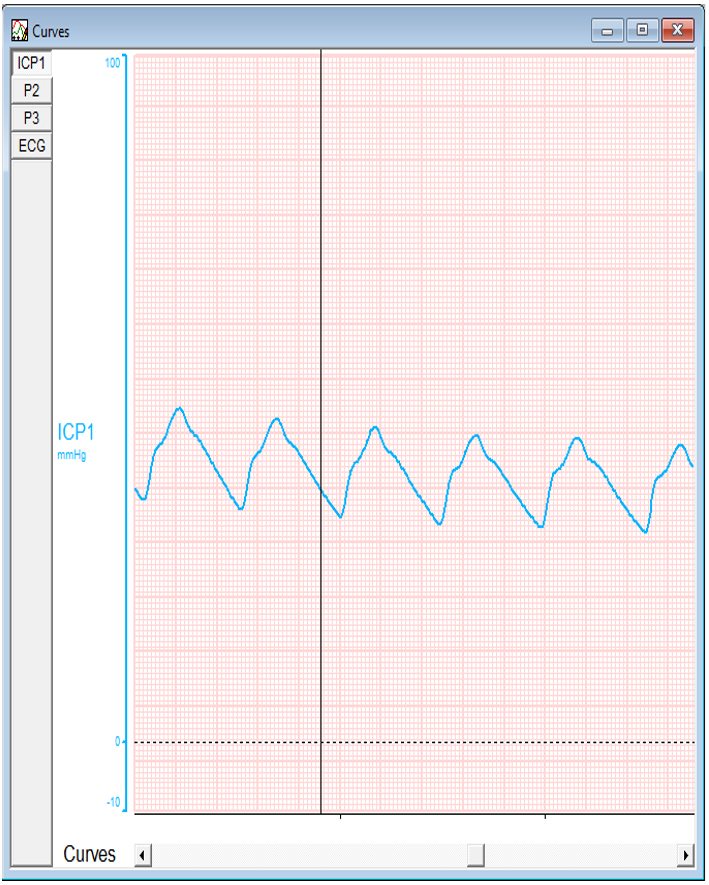

Repeat CT showed enlargement of frontal contusion. ICP was approaching to 37 and ICP A is 14 that is reflected the abnormal waveform.

Pre Operative Readings

P2 is taller than P1: Poor Compliance

Upon lifting the bone flap there is a minimal drop in both values but still in high range.

As durotomy is done, both ICP and ICP A again plummet to the normal values, also evidenced by the graph.